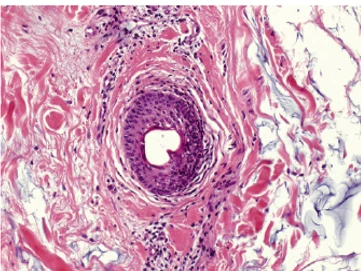

Рис. 2. Окрашивание гематоксилин-эозином, x 20, E - эпидермис, LY - лимфоциты, PZ - плазмоциты, EG - эозинофильные гранулоциты, FM – инородный материал.

Juvéderm® 30HV. Слабое или средне выраженное хроническое воспаление, повышенный уровень лимфоцитов, плазмоцитов и эозинофилов: LY, PZ, EG.

Restylane® Perlane. Выраженное хроническое воспаление, значительная инфильтрация лимфоцитами, плазмоцитами и эозинофилами: LY, PZ, EG.

Teosyal® Deep Lines. Ярко выраженное хроническое воспаление, аномально ярко выраженная инфильтрация лимфоцитами и плазмоцитами: LY, PZ, EG.

Belotero® Intense. Гистоморфологическая реакция воспаления отсутствует. Равномерное распределение материала.

Результаты эксперимента показали отсутствие признаков воспалительной реакции в ответ на введение только двух филлеров на основе ГК – Belotero® Balance и Belotero® Intense (рис. 1, 2), в то время как все другие филлеры показали признаки хронической воспалительной реакции. Значительного различия между результатами исследования образцов, взятых через 14 и 30 дней после введения, отмечено не было.